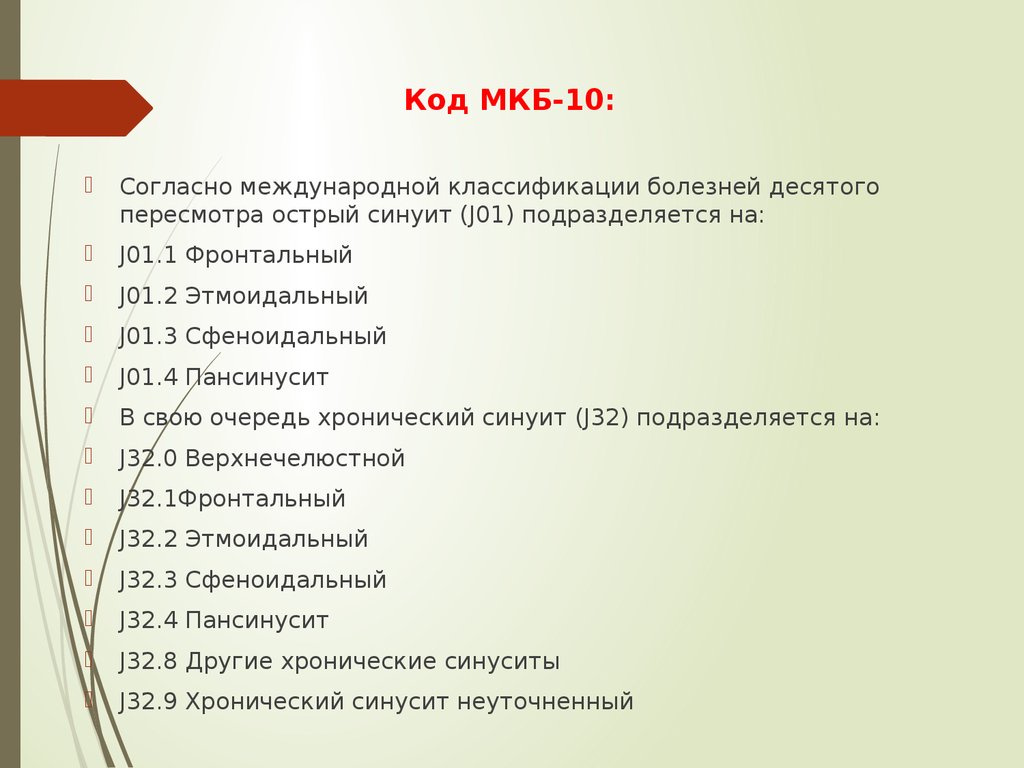

Код мкб 10 атерома головы

Код мкб 10 атерома головы 109 фото